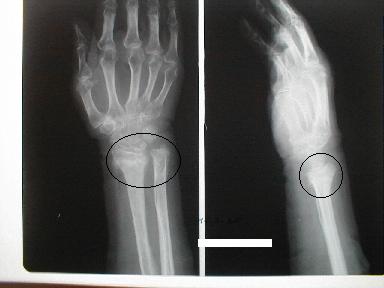

40811031.jpg左の写真

丸の上にバーを乗せるイメージ